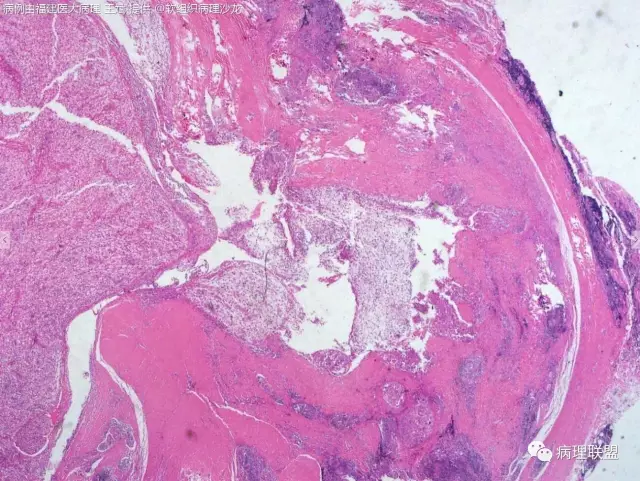

38岁,女性,手部小指背侧皮下肿物,3×2cm(病例由福建医大病理 王斌提供,致谢!)

血管瘤样纤维组织细胞瘤的肿瘤周围有淋巴细胞鞘,结节状分布,有假包膜,出血囊性变的为其主要特点,当然少数病例可以没有出血囊性变却出现粘液变。肿瘤细胞有一定异形性,属于低度恶性或交界性,最好做个FISH,看看有没有EWSR1-CREB1融合基因,刚查了一下,血管瘤样纤维组织细胞瘤还有另一种EWSR1-ATF1融合基因,无论是哪种,用EWSR1分离探针就可以检测